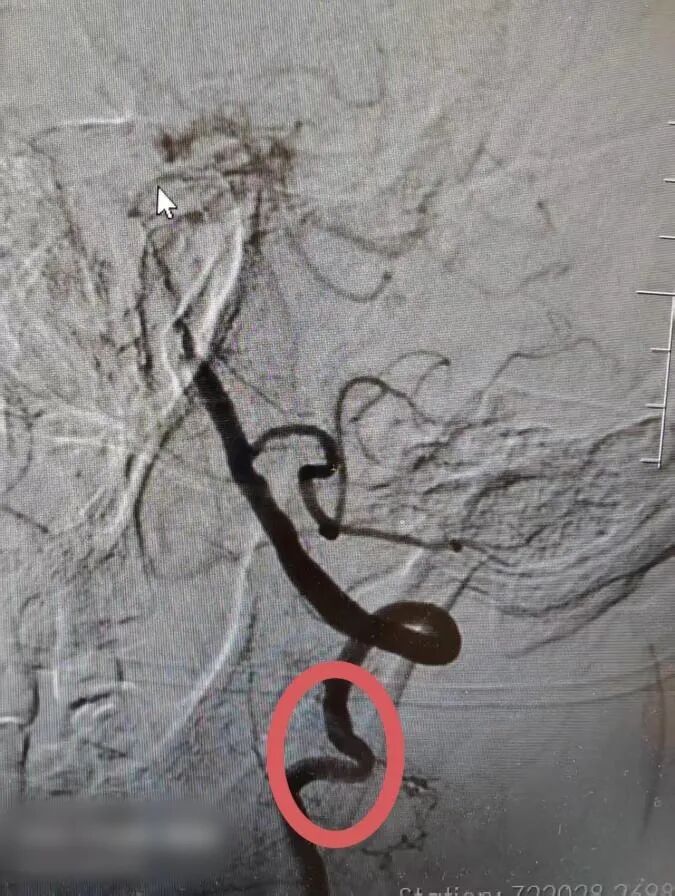

左椎V2段起始段扭曲

左椎动脉起始段扭曲

60岁的陈先生(化名)怎么也没想到,走路不稳、说话含糊、一侧身体渐渐不听使唤这些信号,会将他的人生航道推向一片险滩。从外院转至我院时,影像结果揭示了严峻的现实:多发性脑梗死,而“堵塞”的核心,正位于生命供血的“关键枢纽”——基底动脉下段与椎动脉融合处,重度狭窄。更棘手的是,他的血管天生细长且极度迂曲,犹如一条扭曲淤塞的河道,想要疏通,每一步推进都如履薄冰,风险极高。

手术日,无影灯下安静而专注。在麻醉团队的精密护航下,樊小兵副主任医师凝神屏息,操控着微导管与导丝,开始在那些迂曲狭窄的“河道”中穿行。每一毫米的推进,都是技术与耐心的考验。最终,导丝成功穿越险径,抵达目标区域。清晰的脑血管造影进一步明确了病变,随后进行的血管内介入治疗,顺利重建了血流通路。那一刻,生命航道的关键梗阻被成功解除。